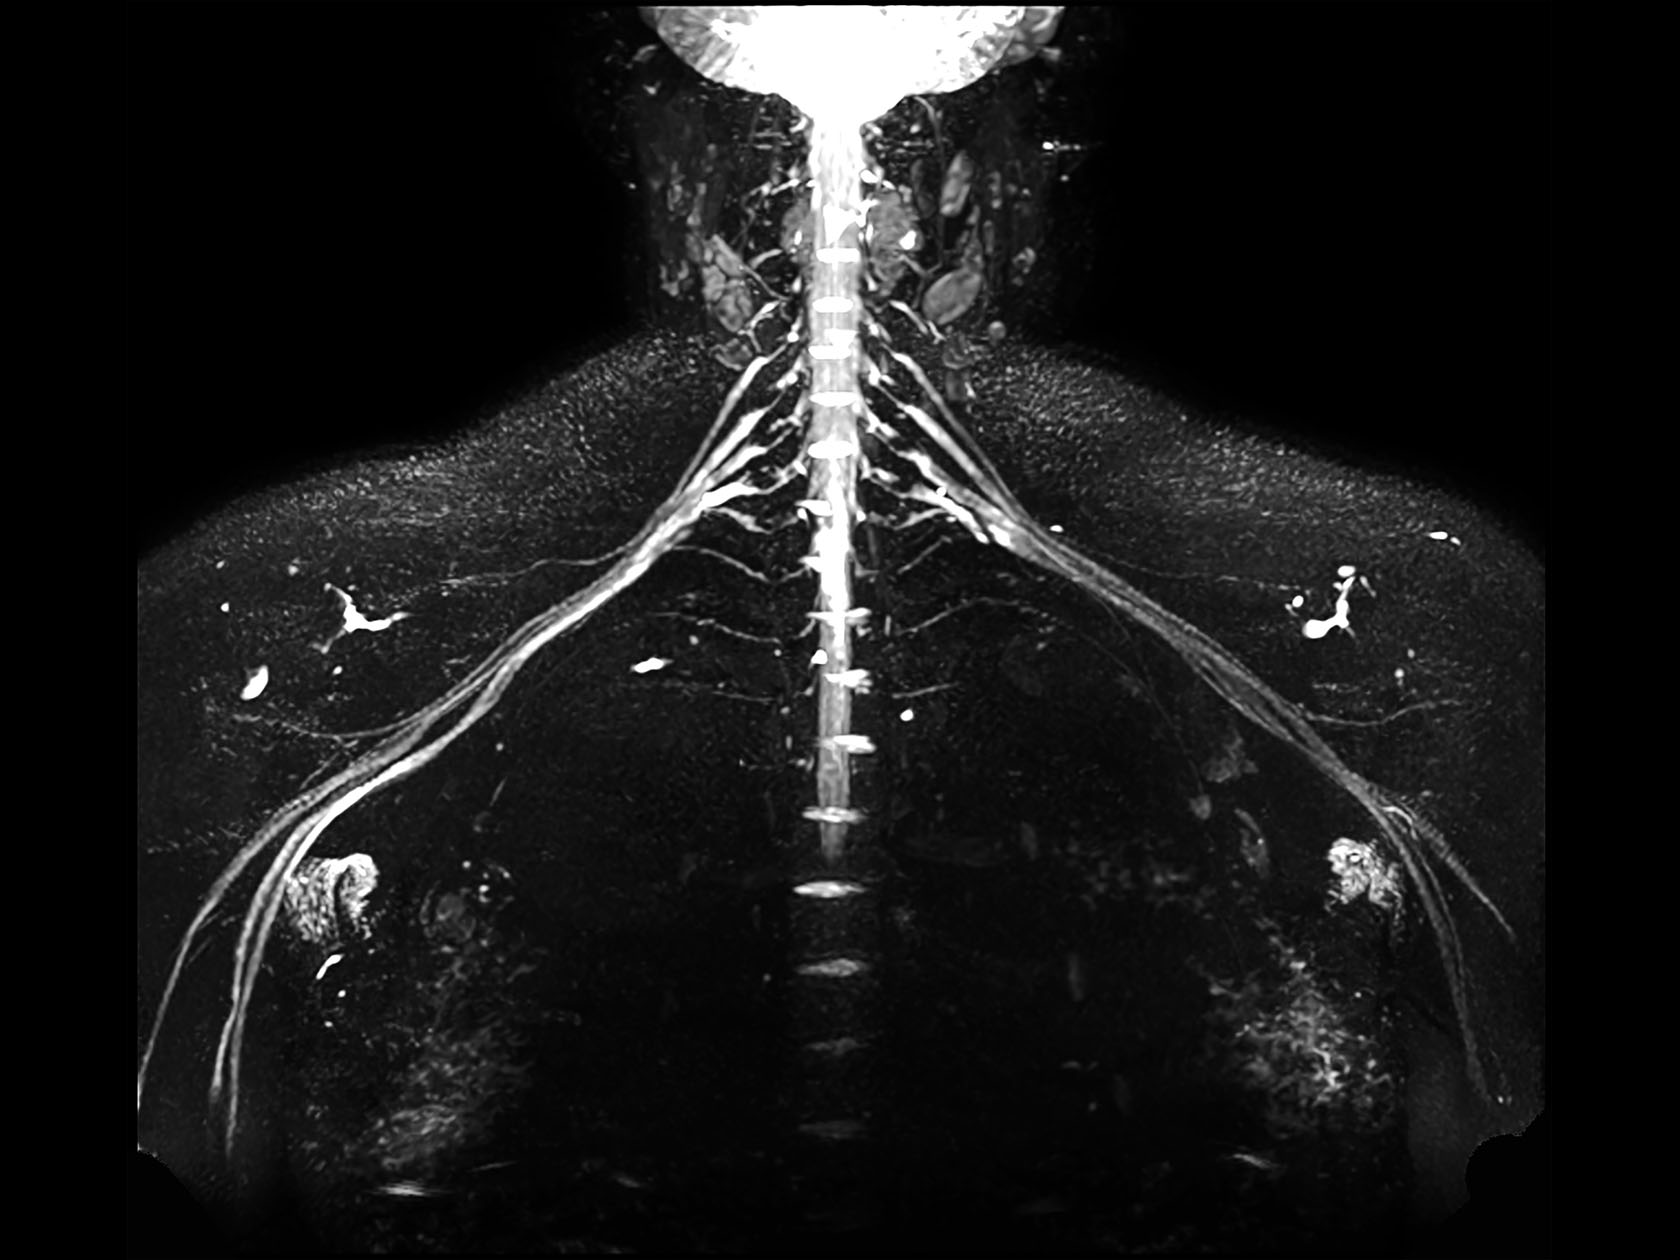

Non-invasive nerve plexus imaging

• Clinical Application